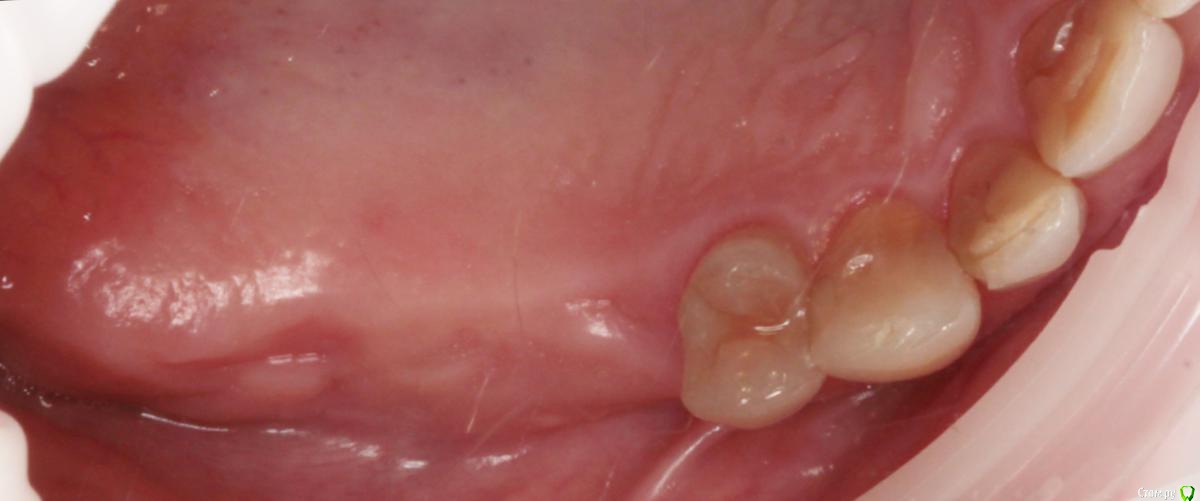

1) имплантация в позиции 15,17 з с закрытым синусом и незначительной НКР

3) имплантация с ССТ в позиции 24 з ( после дистализации 25,26 з), в области 27 з на момент  операции был гнойный синусит, отложили